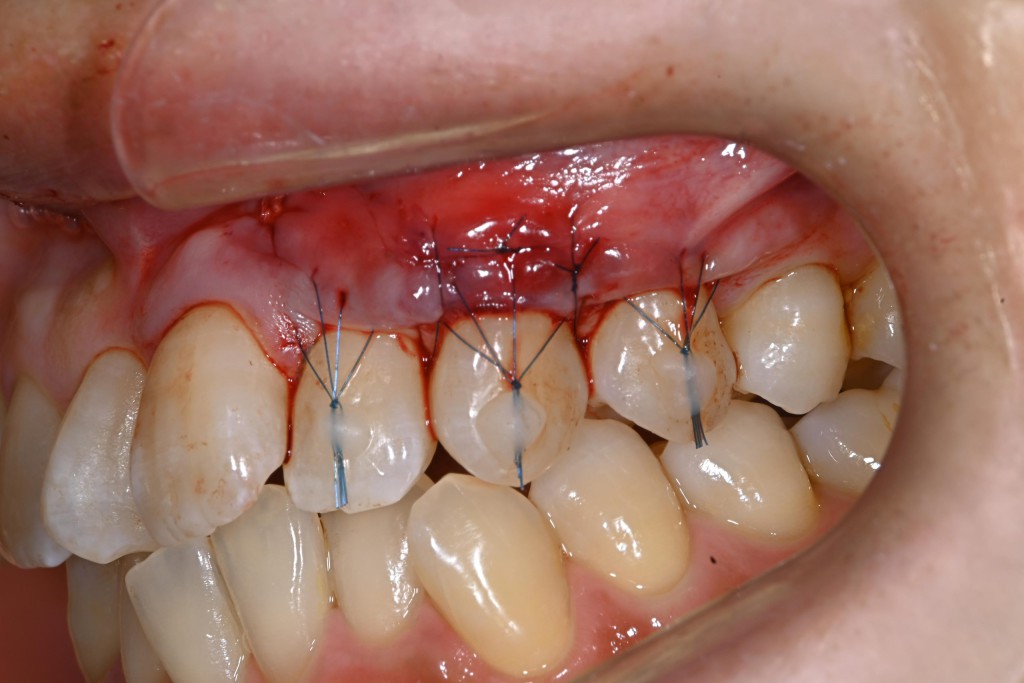

さて今回は上顎の歯肉退縮の症例を紹介します。

| 治療内容 | 歯肉退縮治療(VISTA) |

| 治療期間 | 3ヶ月 |

| 治療費用 | 8万円( 税抜 ) |

| 副作用・リスク | 外科処置が伴うため、術後の疼痛・腫脹・出血・咬合痛などを生じる事があります。 麻酔を行う場合、腫れやむくみを生じる事があります。 |